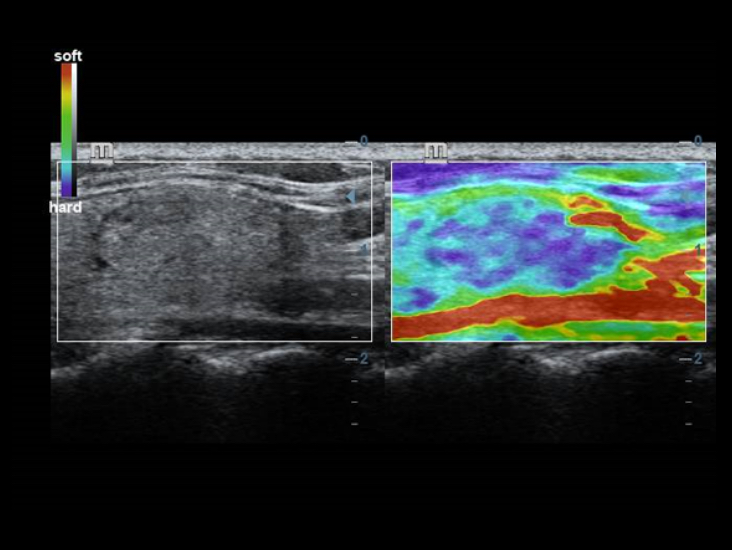

Transductores ComboWave